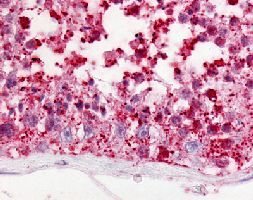

Immunohistochemistry (Formalin/PFA-fixed paraffin-embedded sections)

Immunohistochemical (Formalin/PFA-fixed paraffin-embedded sections) staining in human testis with GPR18 polyclonal antibody (Cat # PAB16532). - Gene Info — GPR18